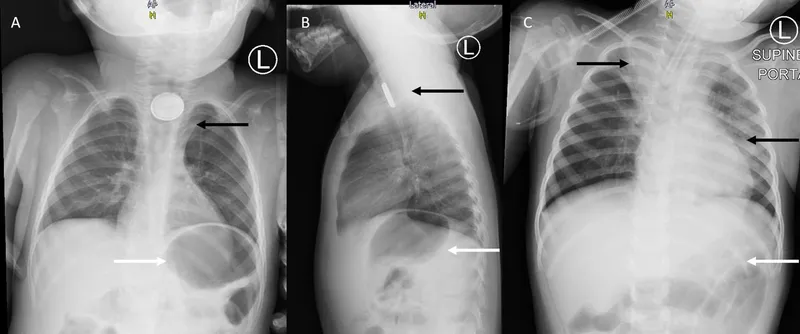

- Button Batteries: Urgent!

- Mechanism: Liquefaction necrosis, electrical discharge.

- ⚠️ Esophageal: Remove <2 hrs. X-ray: Halo (AP), step-off (Lat).

- Complications: Perforation, fistula.

⭐ Button batteries lodged in the esophagus require emergent removal, ideally within 2 hours, due to the high risk of liquefaction necrosis and perforation.

- Esophageal button batteries: EMERGENCY! Remove within 2-6 hours to prevent necrosis/perforation.